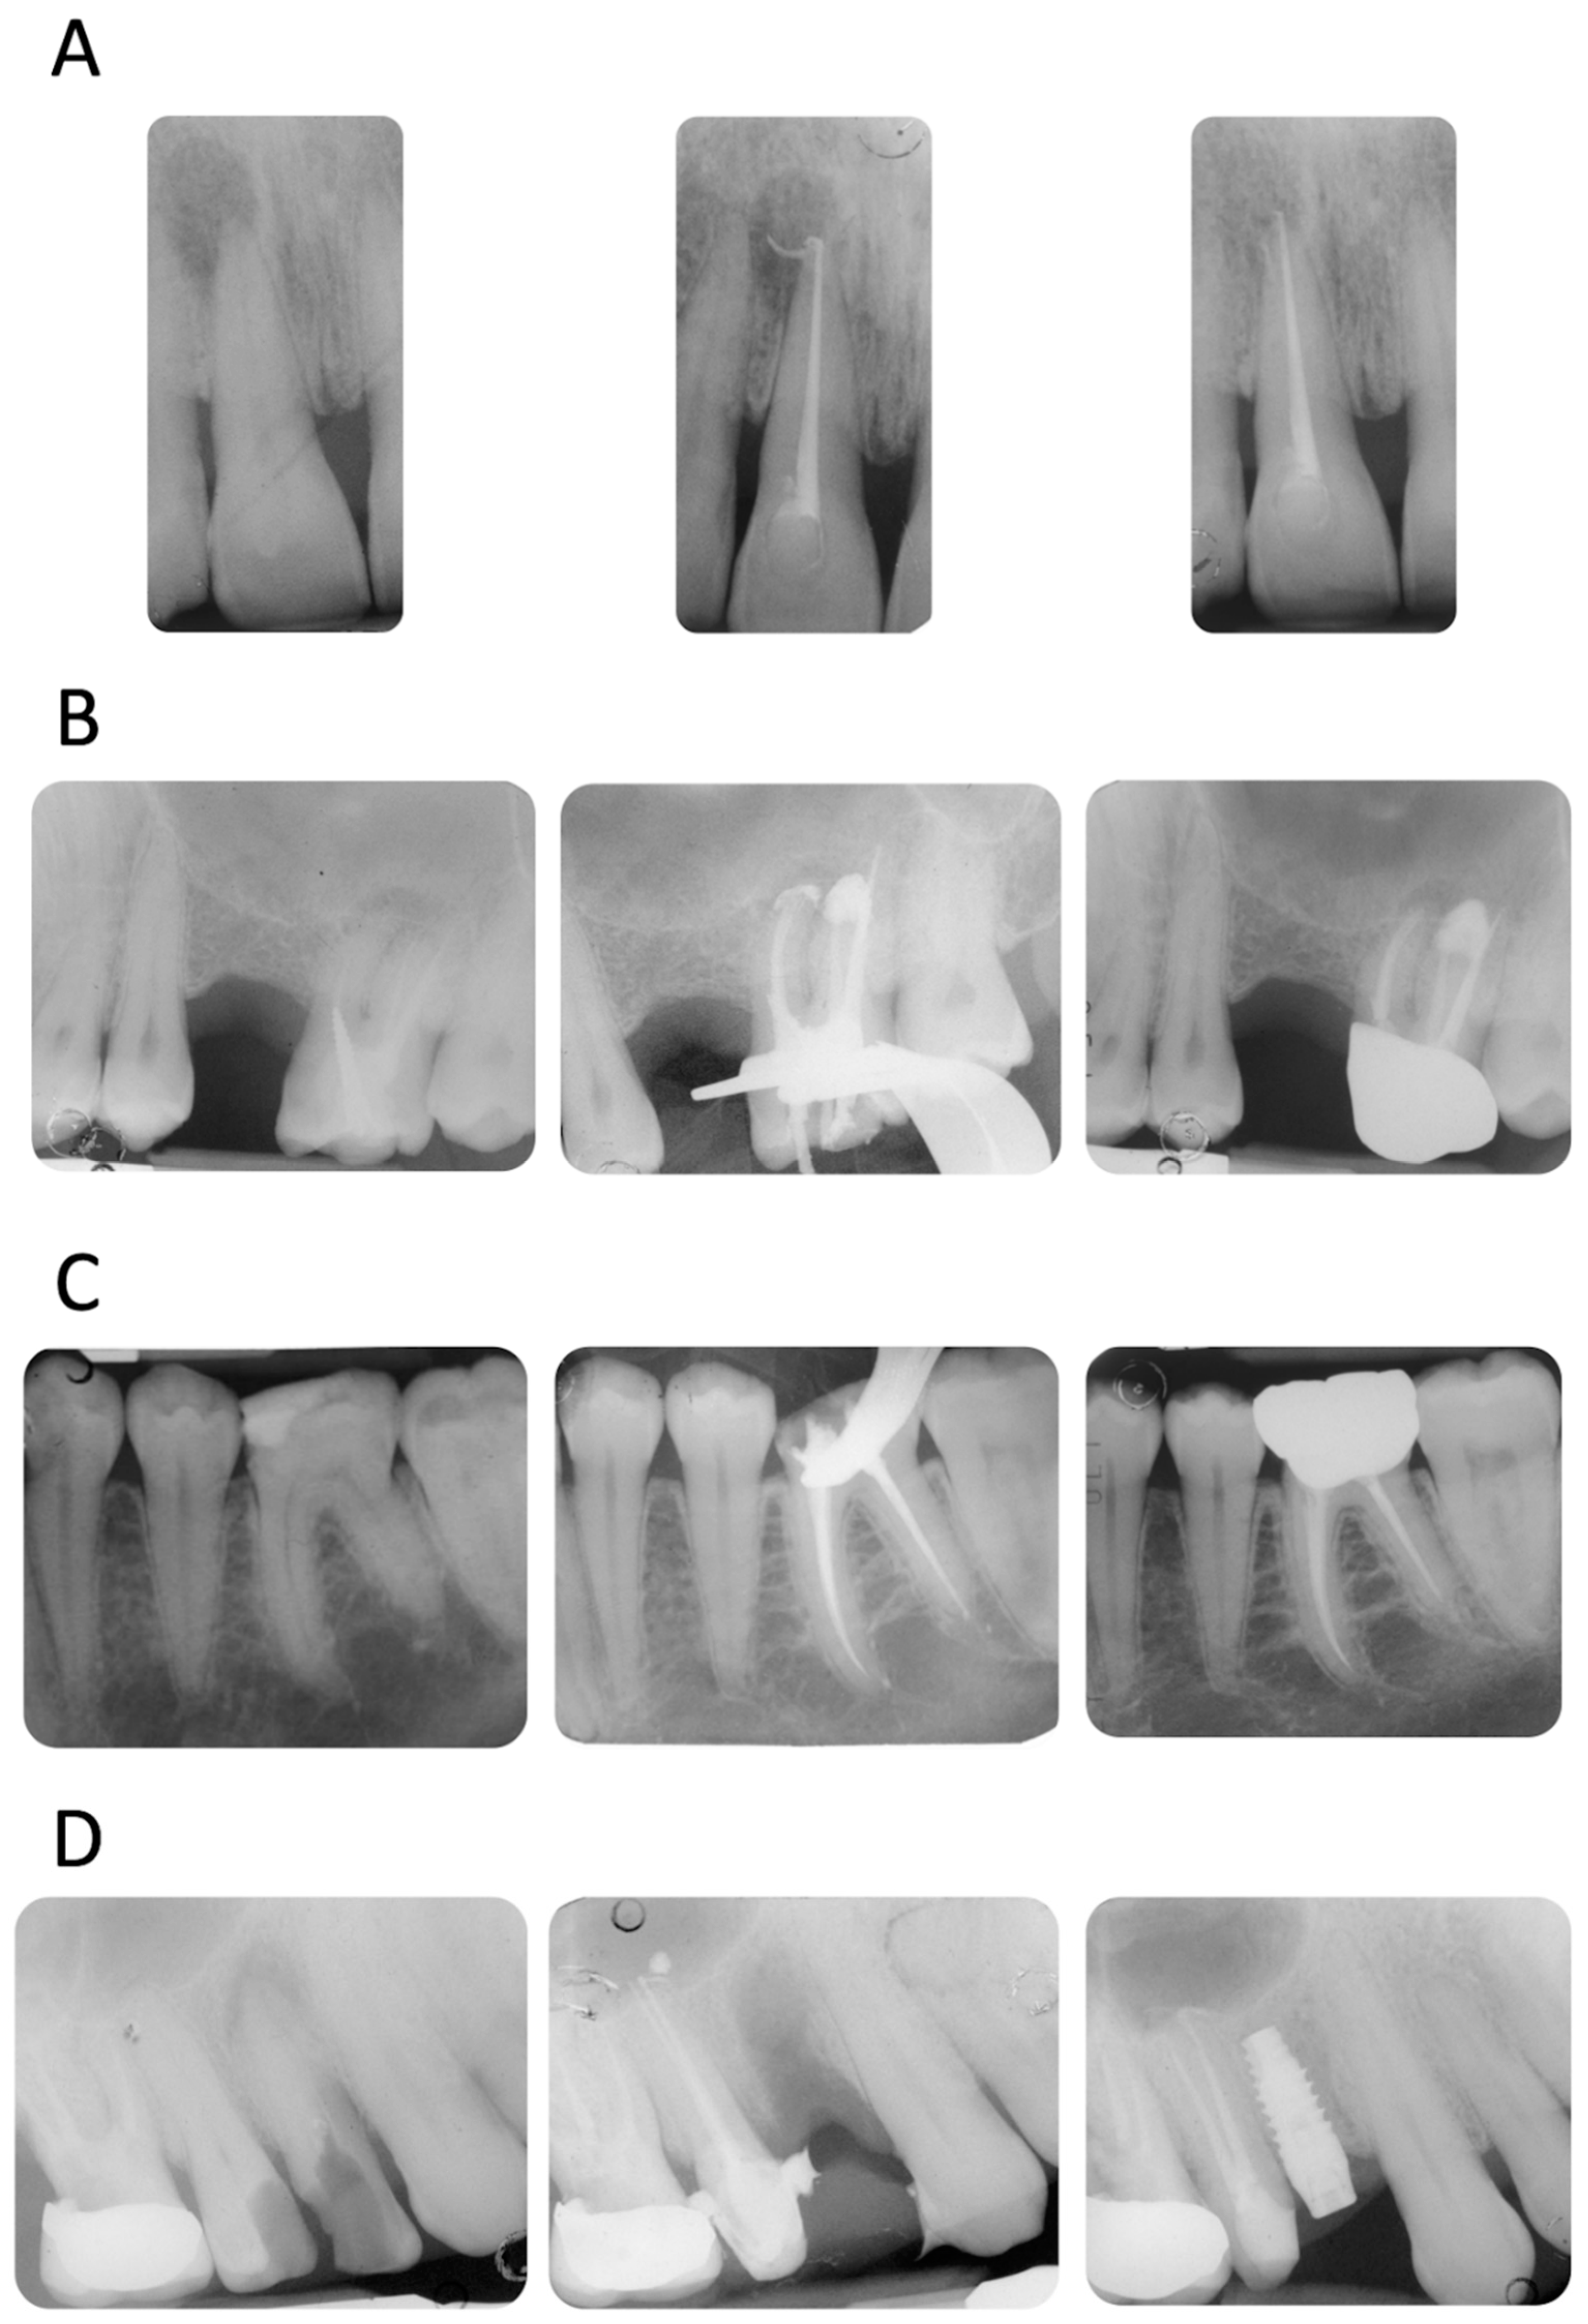

1. Introduction

2. Materials and Methods

2.5. Root Canal Filling Procedures

2.7. Radiological Evaluation